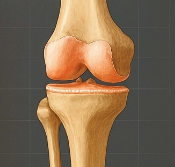

무릎 연골 손상 증상 무릎 연골 손상이란 무엇인가?

무릎 연골은 대퇴골(허벅지뼈)과 경골(정강이뼈) 사이에 존재하며, 충격을 흡수하고 관절을 부드럽게 움직이게 도와줍니다. 연골이 마모되거나 찢어지면 관절 간 마찰이 심해지고, 염증과 통증이 발생합니다. 대표적인 형태는 다음과 같습니다.

- 반월상연골 손상: 무릎 중앙의 C자 형태 연골이 찢어짐

- 연골연화증: 무릎 연골이 말랑해지며 기능 저하

- 연골 마모: 반복적 충격으로 연골이 닳아 없어짐